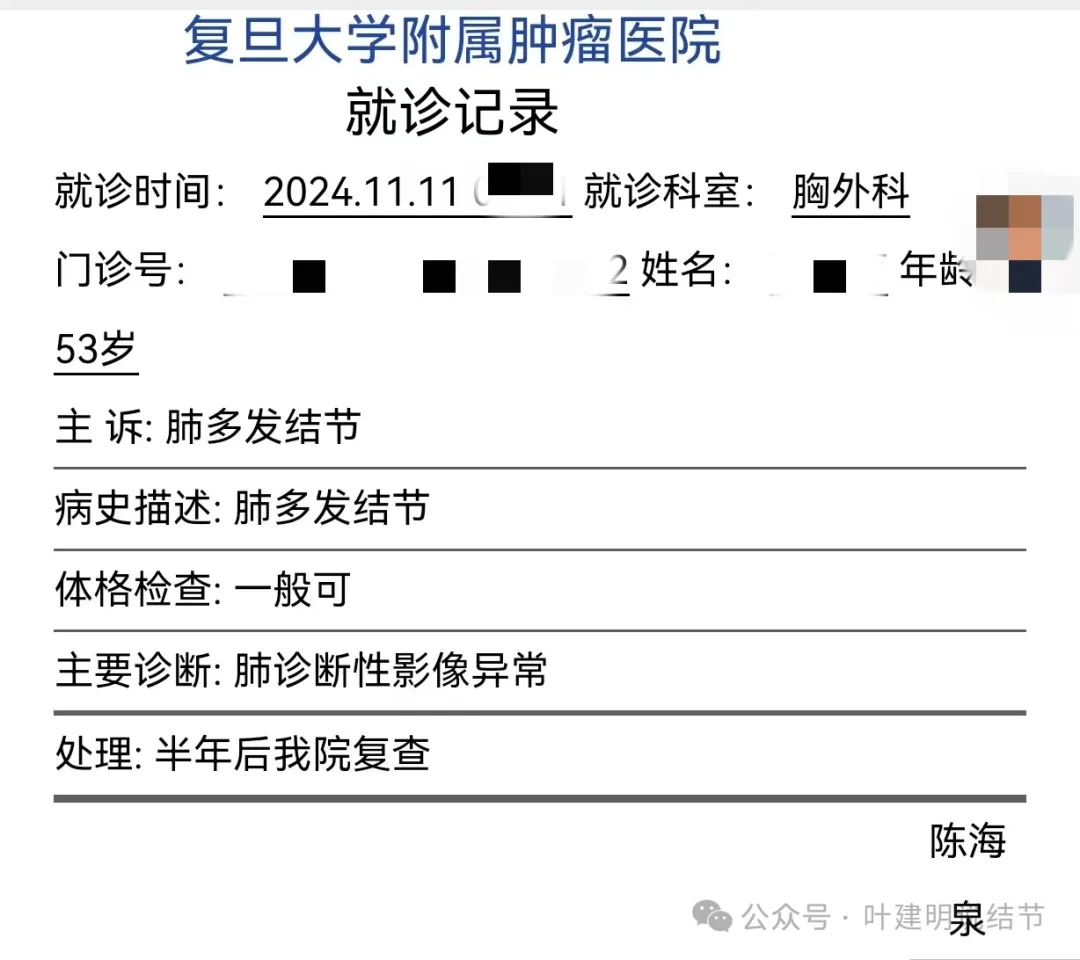

上海复旦肿瘤医院陈海泉教授诊断是肺诊断性影像异常,建议半年后复查。